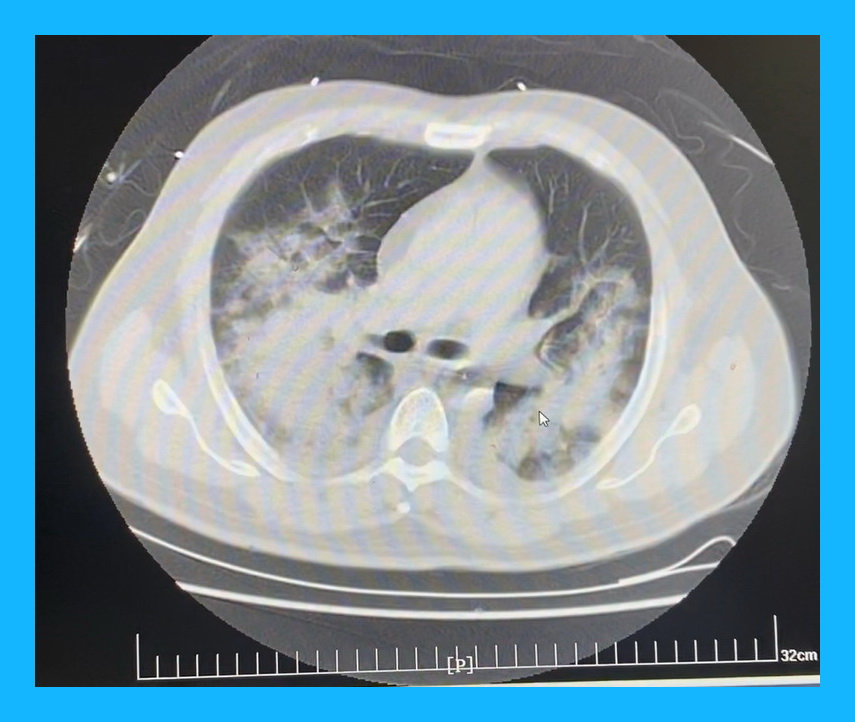

急性心肌梗死心脏破裂在急性期手术,由于心肌处于严重的炎症水肿状态,早期很多病人因此造成切口出血下不了手术台;美国STS数据库显示,如果在发病4周后手术,患者的病死可能性为13.2%,所以目前大多数倾向择期手术;但临床中只有5%的患者可以保持血流动力学稳定,所以急诊手术是唯一有效的救命方法;而这个患者更为严重的是,由于没有及时就医,双肺严重水肿,X片上双肺已经全部发白,血压只能靠IABP勉强维持。